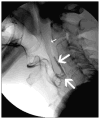

Cross-sectional imaging plays an important role in the evaluation of the retropharyngeal space (RPS) and the prevertebral space (PVS). Because of their deep location within the neck, lesions arising within these spaces are difficult, if not impossible, to evaluate on clinical examination. This article details the cross-sectional anatomy and imaging appearances of primary and secondary diseases involving the RPS and PVS, including metastasis and spread from adjacent spaces. The role of image-guided biopsy is also discussed.